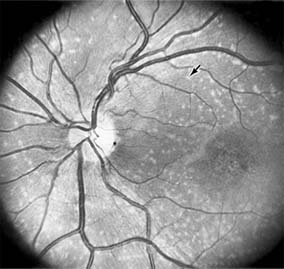

Presumed Ocular Histoplasmosis Syndrome (Figures 10-5, 10-6 and 10-7)

In this disease, serous and hemorrhagic detachments of the macula are associated with multiple peripheral atrophic chorioretinal scars and peripapillary chorioretinal scarring (see Chapter 7). The syndrome usually occurs in healthy patients between the third and sixth decades of life, and the scars are probably caused by an antecedent subclinical systemic infection with Histoplasma capsulatum. The macular detachments are due to subretinal neovascularization, and the visual prognosis depends on the proximity of the neovascular membrane to the center of the fovea. If the membrane extends inside the foveal avascular zone, only 15% of eyes will retain 20/40 vision. A macular scar may change over time, and 10% of patients with normal maculae will develop new atrophic scars in this region. The relative risk of developing macular subretinal neovascularization in the second eye of an affected patient is significant, and these patients should be instructed in the frequent use of the Amsler grid and the importance of prompt examination when changes are detected.

Figure 10-5

Figure 10-5: Presumed ocular histoplasmosis syndrome with active disease (large arrows) and an inactive pigmented macular scar (small arrow). Peripapillary pigmentation (curved arrow) is also present.

Figure 10-6

Figure 10-6: The early fluorescein angiogram shows an inactive hypofluorescent scar (small arrow) and the characteristic lacy hyperfluorescence of subretinal neovascularization (open arrows).